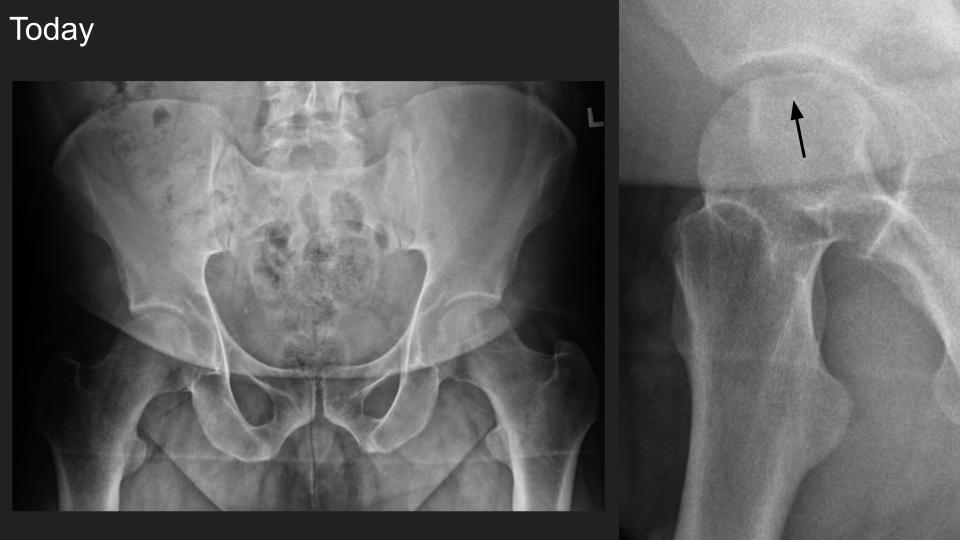

No history of trauma, acute onset of pain, reported as subhcondral fracture.

There is new subtle smooth articular flattening visible in the Dunn view only

Is there real mixed lucency and sclerosis, or is this shine through of the acetabulum? Do you think there might be evolving AVN, or just subtle articular collapse related to prior fracture without AVN?  Would you recommend follow up MRI? Would you recommend DEXA?